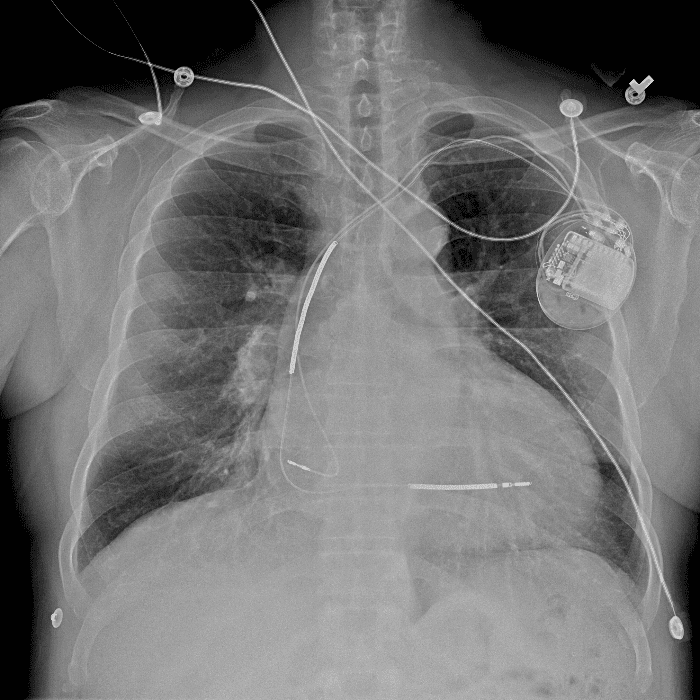

Practice Cases